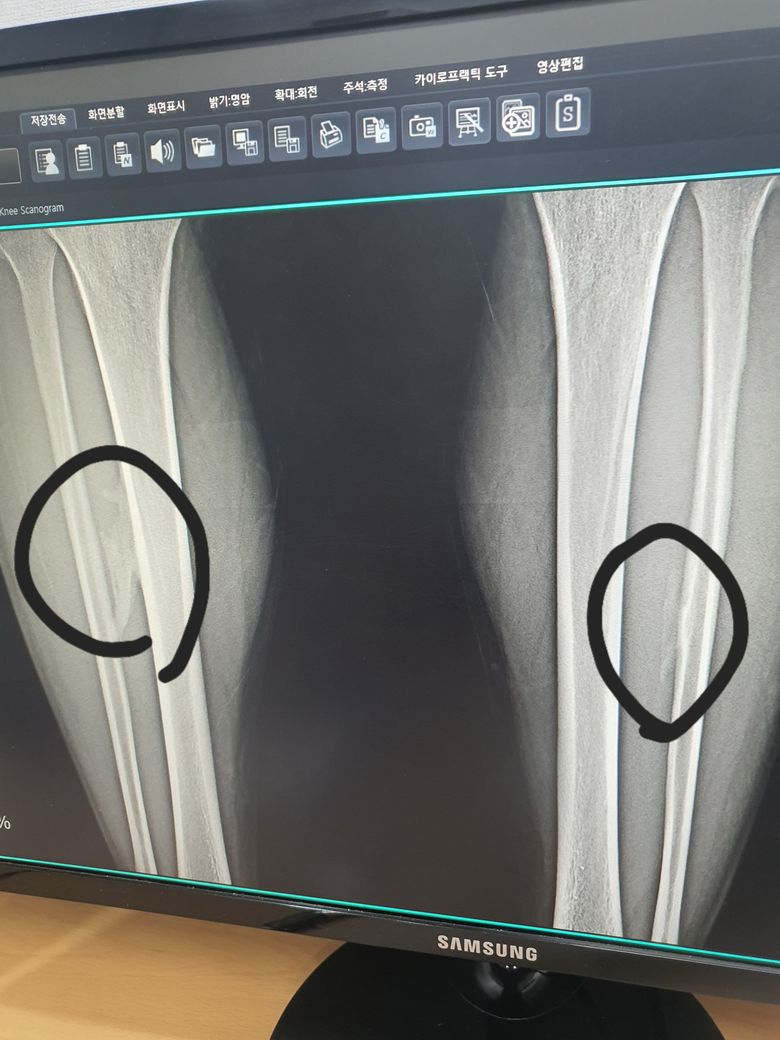

동네병원에서 우연히 찍었는데 양쪽 정강이에 종양이 있다고 합니다 크기는 오른쪽 기준 9~10센치 정도구요

골연골증이나 경비결합외골증??? 이라는데 선생님들 한번 봐주세요 혹시 MRI찍어야 되나요?

골연골종이나 경비결합외골증 진단을 받았다면 양성 종양일 가능성이 큽니다 크기가 9~10cm라면 추가 검사를 위해 mri촬영이 필요할 수도 있으니 정형외과 전문의와 상담해보시는 것이 좋습니다 특히 통증이 있거나 크기가 계속 커진다면 정밀 진단이 중요합니다!